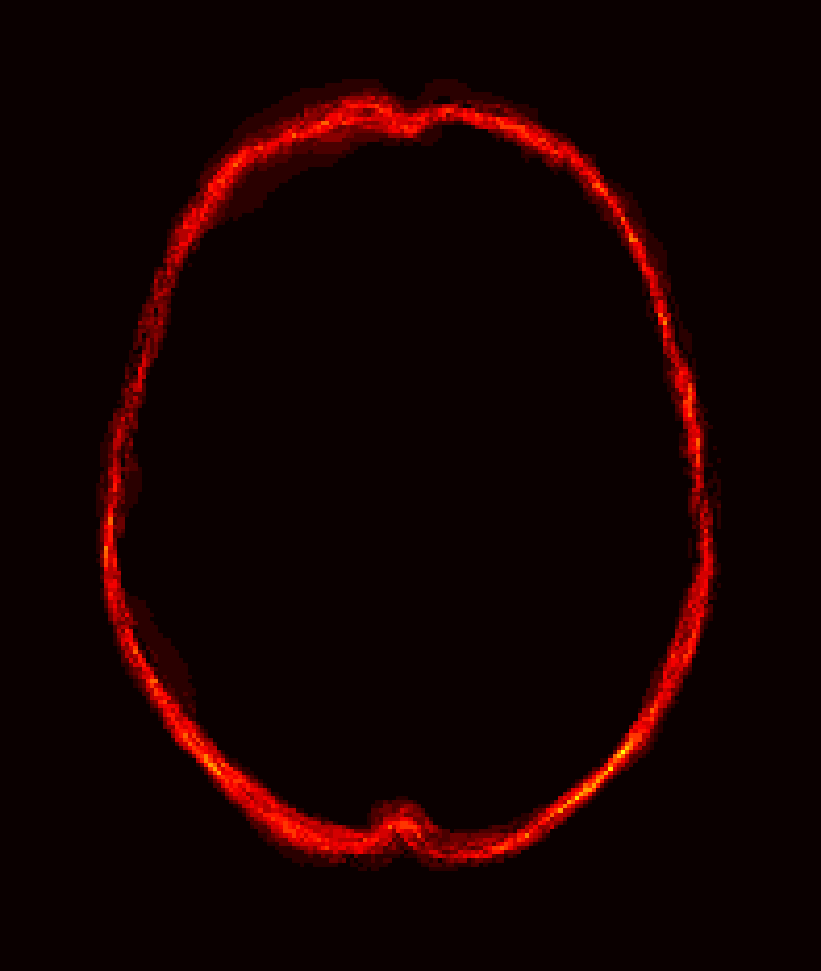

Fig. 1 shows example images from each dataset to illustrate image variability. IBSR and LPBA40 contain images from normal subjects and include large portions of the neck; BRATS has very low out-of-plane resolution; and the TBI dataset contains large pathologies and abnormal skulls.

Refer to caption

Figure 1: Illustration of image appearance variability on a selection of images from each (evaluation) database. From top to bottom: IBSR, LPBA40, BRATS and TBI.